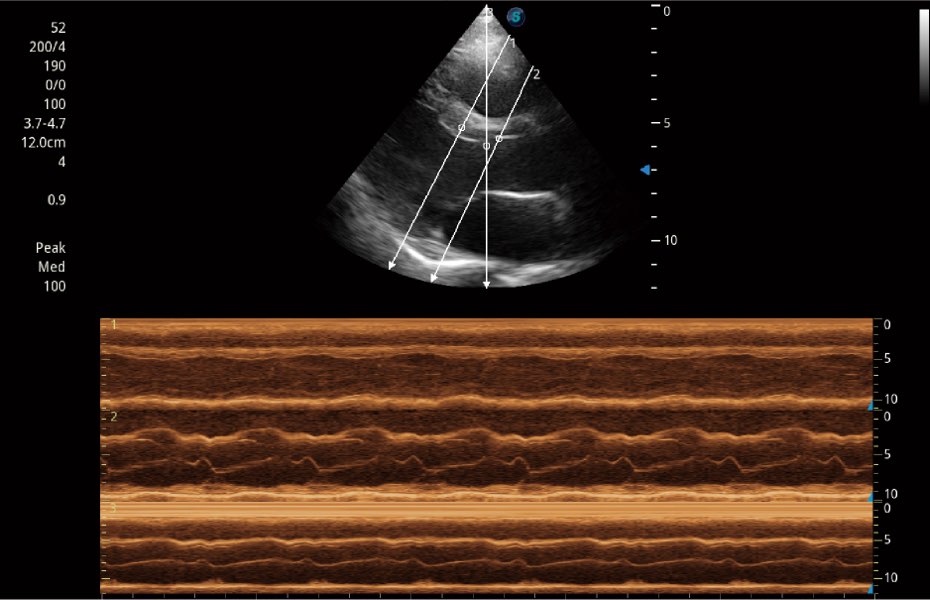

Przy pracach nad aparatem ProPet 60 uwzględniono najważniejsze preferencje i potrzeby weterynarzy, oferując finalnie przystępne cenowo i odpowiednio wyważone połączenie znakomitej precyzji klinicznej, zwiększonej wydajności i przemyślanego przebiegu pracy, niezastąpione w codziennej praktyce weterynaryjnej. Dzięki dostępowi do pełnej gamy głowic HD rozwiązanie to spełnia wszystkie potrzeby w zakresie obrazowania, umożliwiając wykonywanie badań jamy brzusznej, małych narządów, ortopedycznych, badań podczas rozrodu, a nawet badań serca i klatki piersiowej, a to wszystko przy doskonałym stosunku jakości do ceny.